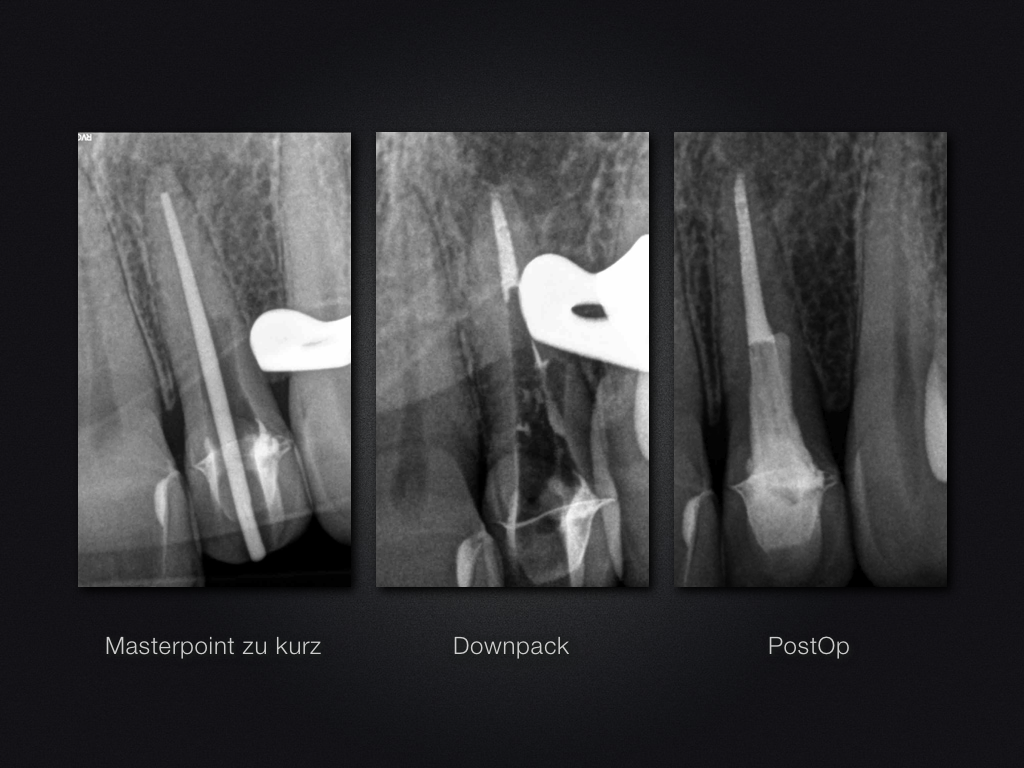

22D.005

Unverhofft kommt oft